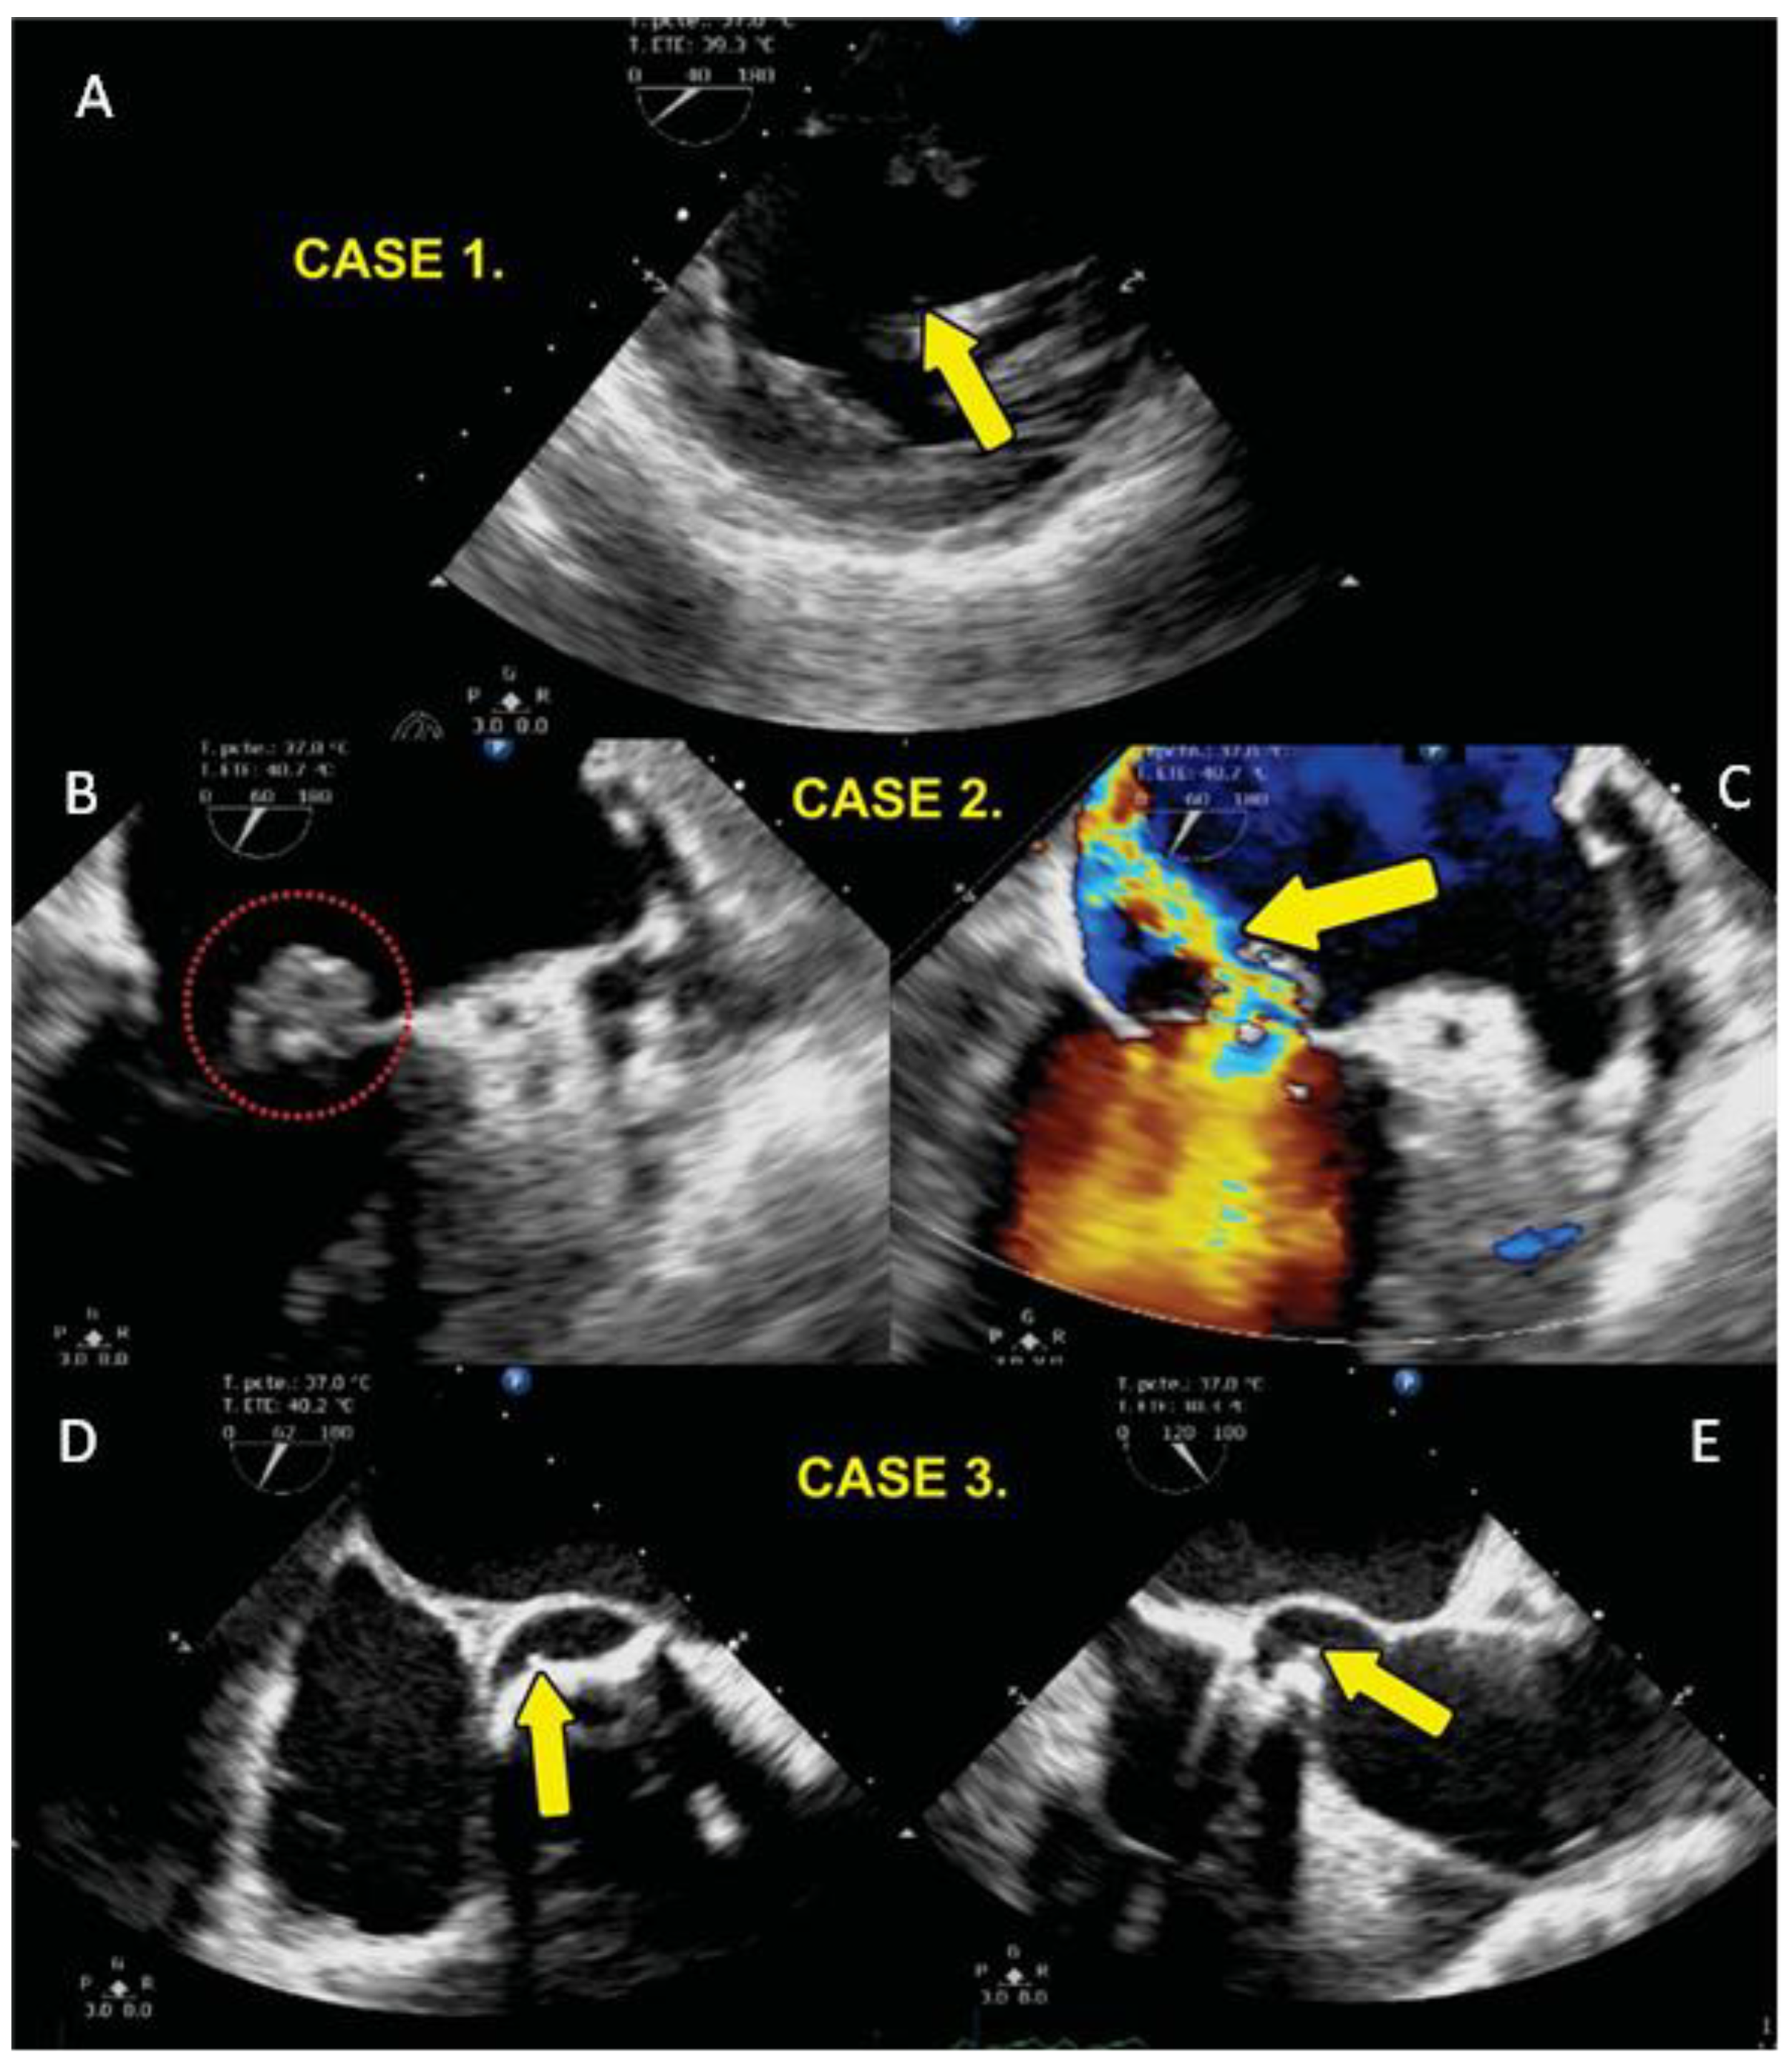

| 1 | 55 | F | 20 | 2009 diagnosis of Arteritis de Takayasu plus bicuspid aortic valve SAH 1999 AVR by severe AoI (Medtronic Hall). | Endocarditis in 2016. univalve prosthetic valve with pannus and abscess with tissue destruction at level of interventricular septum with bacterial growth with Staphylococcus aureus and epidermidis. Surgery AVR and implantation of, dual-chamber pacemaker, by complete BAV, she had ischemic stroke and left hemiparesis with evolution with reduced heart failure LVEF 25% died in 2017 one year after surgery. | yes |

| 2 | 67 | M | 30 | 2019 DAoI and AoI severe bicuspid aortic valve LV systolic and diastolic dysfunction LVEF 20%, smoking. | 2020 native valve endocarditis with mobile vegetation of left non-coronary valve plus ascending aortic aneurysm, Surgery AVR Medtronic Hall with bacterial growth with Streptococcus viridansj. 2024 normal functioning prosthesis, LVEF 57%. | no |

| 3 | 78 | F | 24 | DAoI and stenosis Ao, tri-valve Aortic valve. 2019 March she received intervention with Transcatheter aortic valve implantation (TAVI) Portico 25 mm plus Boston Scientific DDD Pacemaker Tachycardia Bradycardia Syndrome Comorbidities: Smoking, systemic arterial hypertension, dyslipidemia. | 2019 April she had TAVI endocarditis with vegetation in the aortic valve. Mitroaortic junction abscess plus aortitis aortic wall abscess. Valve crop Enterobacter cloacae, Klebsiella Oxytocic She was treated with aortic valve explanation surgery, ascending aorta resection. Bentall and Bo, MVR Edwards Peri mount. Mitroaortic command surgery. 2024 she is live LVEF 40%. | no |